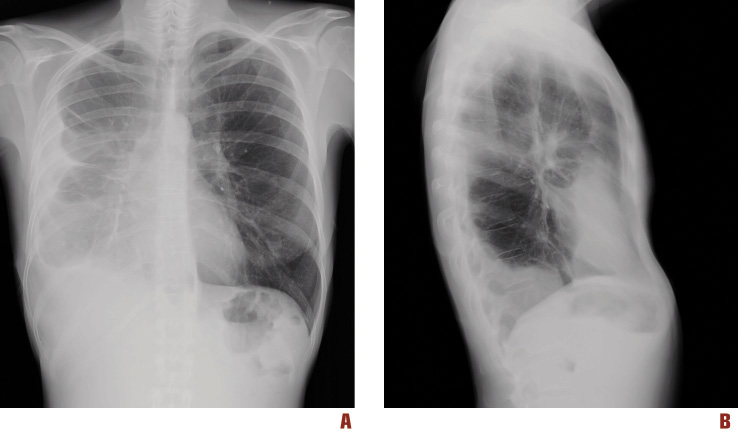

• A The Posterior Anterior View Of The Chest Radiograph Demonstrating The Large Right Sided Pleural Effusion With Consolidation In The Right Lung Base Ppt Download

Up to this point there was no history of metastatic disease.

Mesothelioma is the most common type of primary pleural tumor and is associated with mpe in more than 90 of cases. They are usually found in the context of gas or blood in the pleural cavity and do not exclude a malignant cause. The patient went on to have a pleural aspiration which demonstrated the presence of malignant cells secondary to prior breast cancer.

When faced with a large unilateral pleural effusion one should always consider the possibility of a malignant effusion and perform a diagnostic.